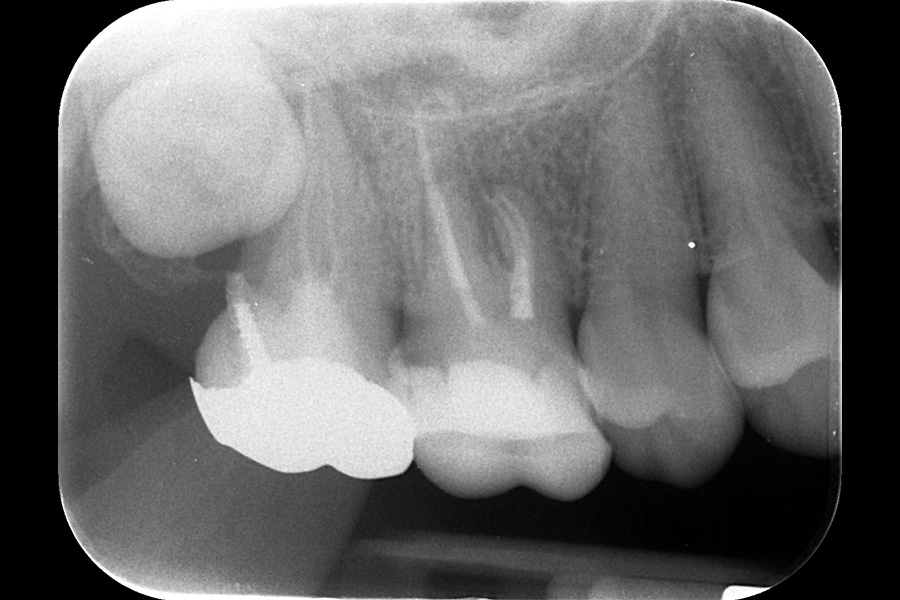

治療前